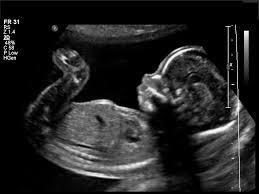

Explain the use of ultrasound. Tissues and organs reflect ultrasound waves back and the time taken for them to return is used to measure their depth. This is used to create an image.

Describe the use of ultrasound. Used to create images of unborn babies (foetal scanning) and of tendons, muscles joints and some internal organs.